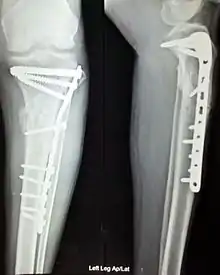

Anterior and lateral view x-rays of fractured left leg with internal fixation

وتشمل المثبتات الداخلية كلاً من مسامير العظام، والشرائح المعدنية، والأسلاك، والمسامير النخاعية كمسمار كونتشر والمسمار النخاعي المعشق.

في عملية الاختزال المفتوح مع التثبيت الداخلي (بالإنجليزية: Open Reduction Internal Fixation - ORIF) يجرى أولاً "اختزال مفتوح" للكسر (أي رد أجزاء العظمة المكسورة إلى موضعها الصحيح جراحياً)، ثم "تثبيت داخلي" أي تثبيت الأجزاء التي تم ردّها باستخدام شرائح ومسامير وغير ذلك من التركيبات.[1][2]